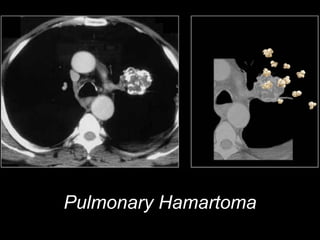

o Popcorn: Hamartoma

Pulmonary Hamartoma